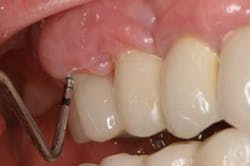

Fig. 3: After using Slimline ultrasonic, cement is removed.